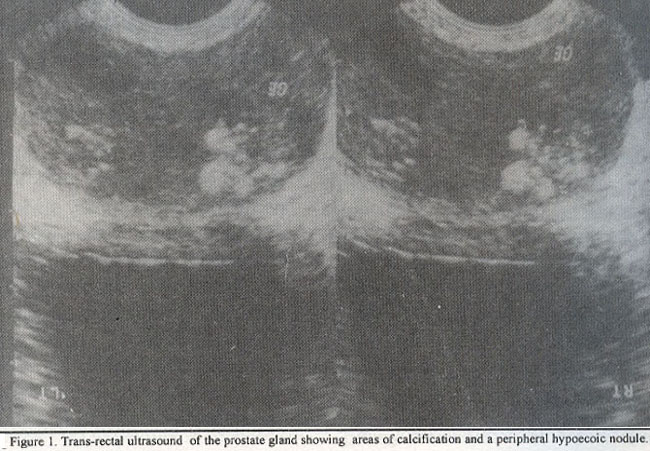

A TRUS was performed which showed multiple areas of calcification and a peripheral hypoechoeic nodule in the left lobe of the prostate (Figure 1).

A tentative diagnosis of Gran P is usually entertained on the basis of symptomatology, physical findings and TRUS. However, it requires histopathology for confirmation10. The symptoms are those of nonspecific prostatitis, few develop a palpable lesion in the prostate on DRE. Imaging findings are non-specific. TRUS is the most frequently used imaging modality and the predominant finding is a hypoechoic peripheral nodule, Some patients may have focal asymmetric flow to the lesion on color doppler ultrasound9,11, On MRI, the lesion appears as a focal low intensity signal12.